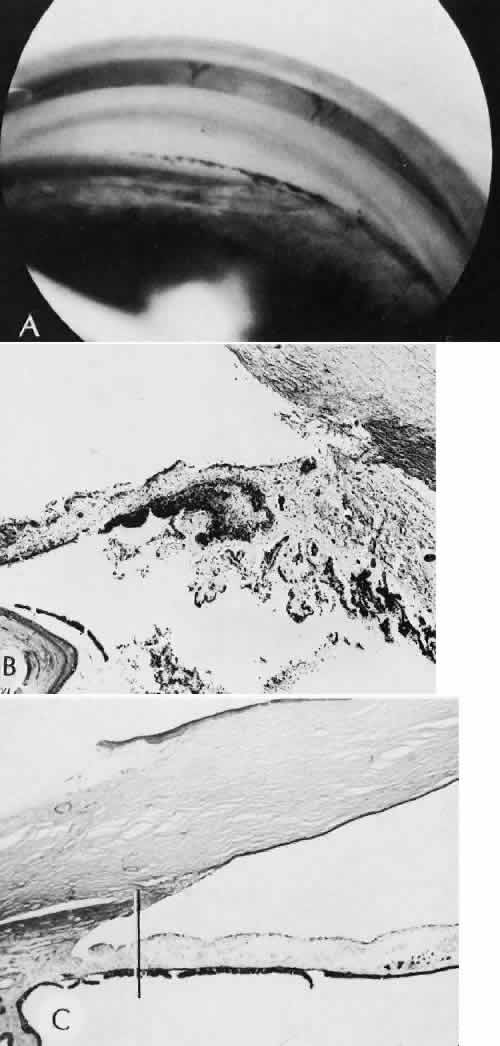

that results in reestablishment of functional ocular anatomy.1–3 The goal of therapeutic intervention in the setting of ocular trauma is to promote the repair process and to allow it to proceed as rapidly as possible and heal as completely as possible without compromising ocular function.4 CELLULAR AND EXTRACELLULAR COMPONENTS The four basic cell types found in wound healing are fibroblasts, vascular endothelial cells, inflammatory cells, and epithelial cells. Specialized cell types that participate in ocular wound healing include corneal endothelial cells, retinal pigment epithelial cells, and Müller cells of the retina. Specific cell populations enter an area of injury under the influence of complex biochemical and biophysical processes involving proteins of the extracellular matrix and the coagulation system. Intracellular proteins, such as tubulin and actin, andmyosin filaments function in cell locomotion. Extracellular matrix proteins, such as fibronectin, laminin, and type IV collagen, orient and regulate cell migration and adhesion.5 Coagulation proteins, such as von Willebrand's factor and plasminogen, alsofunction in regulating the cellular events of healing. Vascular endothelial cells are stimulated to leave their resting state and digest basement membrane, proliferate, migrate, and eventually differentiate under the direction of multiple angiogenic growth factors.6 A wound usually is filled first by a fibrin coagulum. Neutrophils, lymphocytes, and histiocytes (macrophages) enter the wound through fibrin scaffolding to clear necrotic debris and confine toxic or foreign substances. Granulation tissue often is the first type of reparative tissue in wound healing (Fig. 1). Although its composition varies somewhat, small-caliber vascular channels in a delicate collagenous stroma infiltrated by acute and chronic inflammatory cells generally characterize it. This amorphous tissue serves as a template for more definitive repair. Metaplasia is the transformation of a cell from one adult cell phenotype to a second cell phenotype. In advanced wound healing, fibroblasts acquire intracytoplasmic characteristics of smooth muscle cells (myofibroblasts).7 The myofibroblasts are able to contract and bring wound edges together. Vascular endothelial cells proliferate and migrate into the wound from preexisting adjacent vessels. The new “vessel” migrates initially as a solid bulb of endothelial cells. This solid cord of cells will canalize and differentiate into mature arterioles, venules, and capillaries. Fibroblasts grow into the wound in a radial manner but will eventually reorient and secrete collagen along lines of established tissue tension. Epithelial cells are found covering surfaces of tissue. Two distinct types of epithelial cells cover the ocular surface: corneal epithelial cells and conjunctival epithelial cells. Cell replacement is accomplished by stem cells located at the limbus for the corneal epithelium8,9 and at the mucocutaneous junction and possibly throughout the conjunctiva for the conjunctival epithelium.10 Migration and proliferation of surrounding healthy epithelial cells heal surface discontinuity. Apoptosis is a biochemical process leading to programmed cell death. Cell death in apoptosis results from intracellular messages. In necrosis, cell death results from toxic external factors (e.g., hyperosmolality). Apoptosis allows for elimination of entire populations of cells without tissue damage or an inflammatory response.11 Elimination of certain cells is advantageous in embryology (e.g., when scaffolding structures are no longer necessary as with the primary vitreous). In certain neoplastic conditions, however, defects in apoptosis may lead to disadvantageous accumulation of cells. Apoptosis also seems to be highly influential in all types of inflammation, including wound healing. In wound healing, apoptosis may function to control the type and degree of tissue response.12 In the anterior cornea, keratocytes have been observed to undergo apoptosis in response to wounding of the cornea.13,14 Abnormalities of apoptosis may be responsible for such conditions as keloid formation in the skin15 and keratoconus in the cornea.16 Wound healing of highly specialized tissues of the eye has several unique features. CORNEAL HEALING The healing of the cornea is unique relative to other soft tissues, because it lacks blood vessels and because it is lined anteriorly and posteriorly by layers of epithelial-like cells. Epithelial cells of the corneacan produce essential wound healing factors normally produced by platelets.17 Architectural repair is accomplished at the level of the corneal stroma. Abrasions are injuries generally involving only the superficial layer (epithelium) of the cornea (Fig. 2). Abrasions are commonly caused by mechanical injuries or anoxia resulting from contact lens overwear. Some or all of the layers of the surface epithelium are lost, but Bowman's membrane remains intact. After a delay of approximately 1 hour, uninjured epithelial cells at the margin of the wound loosen their intercellular and basal attachments and migrate en masse toward the injured area.18 The shape of the wound margin and the biochemical characteristics of the exposed tissue influence the direction and extent of the migration.19 If the entire corneal epithelium is abraded, migrating epithelial cells derived from the limbal stem cells are able to cover the defect completely within 48 to 72 hours. The epithelium will be much thinner than normal until mitotic division reestablishes normal thickness. Re-formation of epithelial basement membrane may not be detectable for as long as 6 weeks after injury.20 Clinically, the healed wound is transparent. Small defects of Bowman's membrane (Fig. 3) do not heal by fibrous proliferation of the stroma. The defect is filled by proliferating epithelial cells (epithelial facet formation) that reestablish the surface continuity of the cornea. The facet may be seen clinically as a focal, well-demarcated, superficial corneal opacity. A corneal foreign body causes this lesion most often. Penetrating corneal injuries involving at least one third of the stroma (Fig. 4) are covered initially by proliferating surface epithelium that may extend for a considerable distance into the stroma. The extent of corneal epithelial migration is controlled at least in part by contact inhibition of migration once contact with healthy corneal endothelial cells is established.21 Bowman's membrane has elastic properties that tend to pull the anterior margins of the wound apart. Exposure of the relatively dehydrated corneal stroma to tears and blood will cause swelling of the corneal stroma. This swelling of the stroma tends to close the wound. As the stroma heals, new collagen is produced by keratocytes or transformed monocytes. Epithelial cells will regress toward the surface. The repair collagen is different from the native collagen in size and in orientation. The healed wound is densely opaque and obvious clinically, but it may be detected histologically only by the break in Bowman's membrane. Full-thickness wounds of the cornea are associated with retraction of Descemet's membrane and separation of the posterior aspect of the wound (Figs. 5 and 6). Secondary aqueous, a proteinaceous coagulum, may seal the wound posteriorly until healthy surrounding endothelial cells can spread and migrate into the injured area. Mitotic division of the endothelial cells possibly plays an important role in younger patients but probably is not clinically significant in adults. Ultimately, migrated endothelial cells will produce a new Descemet's membrane (Fig. 7).22–25 The portions of Descemet's membrane displaced into the stroma are not resorbed, but remain as the histologic marker of the site of injury. The anterior cellular surface repair of migration and mitosis of epithelial cells is the same as that described for more superficial corneal wounds. The important exception is that with full-thickness injuries, there is a risk of surface epithelial cells migrating along the posterior surface of the cornea or the anterior surface of the iris to the trabecular meshwork. The displaced epithelial cells will cause scarring of the trabecular meshwork and secondary open-angle glaucoma. CONJUNCTIVAL HEALING Conjunctival healing differs from corneal healing because of the presence of blood vessels and a lymphatic system. The conjunctival epithelium heals by migration and mitosis.26 Conjunctival stem cells are thought to originate at the mucocutaneous junction and migrate to the fornix.27 Goblet cells are produced by epithelial progenitors and appear once conjunctival epithelial cell continuity has been reestablished.28,29 The presence of vascular tissue in the substantial propria of the conjunctiva allows for the formation of granulation tissue and scar tissue, as found in soft tissues elsewhere. SCLERAL HEALING The sclera itself does not participate directly in wound healing. Partial-thickness injuries are healed by formation of granulation tissue from the epi-scleral tissue in external wounds or from uveal tissue in internal wounds (Fig. 8). Full-thickness defects of the sclera heal by granulation tissue originating in the episcleral tissue and uveal tract. Mitomycin is used in filtering procedures specifically to prevent the formation of granulation tissue and promote establishment of an aqueous fistula.30 SURGICAL LIMBUS HEALING Currently, there is a trend for the site of the cataract wound to shift from the limbus to the peripheral cornea31 to reduce induced astigmatism32 and to shorten the natural history of cataract wound healing.33 The healing of the wound is similar to that found in central corneal incisions. Healing at the site of a limbal surgical incision involves a combination of the features of repair of the cornea, conjunctiva, and sclera (see Fig. 5). Conjunctival epithelium will heal over an area of granulation tissue originating from the substantia propria of the conjunctiva and the episclera. The granulation tissue seals the wound if the wound edges are well apposed. The remainder of the healing process is similar to the healing of an external scleral wound. Granulation tissue is not formed in the internal portion of the wound because the uveal tract is not involved. The internal wound is healed by endothelial migration and reformation of Descemet's membrane in a manner outlined above for full-thickness corneal wounds.34,35 Because of the lack of blood vessels, the rate of wound healing is slow relative to that of the skin. Whereas an injury to the skin may have regained its tensile strength in 7 to 10 days, injuries to the surgical limbus may require as long as 12 months to regain a stable tensile strength. The tissues of the wound remain structurally weaker than the surrounding uninjured tissue (Fig. 9). The healing of a clear corneal cataract incision proceeds as described above. UVEAL HEALING Wound healing of the posterior uveal tract follows the general principles for healing of vascularized tissue. The iris, however, heals differently. When the iris wound is perpendicular to its circumferential ridges, such as in a typical peripheral iridectomy or iridotomy, the cut edges pull apart. Granulation tissue does not form to close iridectomy incisions probably because of the inhibitory effect of the aqueous flowing through the opening of these small incisions. Iridotomies created by argon laser (Fig. 10) may be anatomically closed by apparent migration of iris pigment epithelium.36,37 LENS HEALING Proliferation and fibrous metaplasia of the lens capsular epithelium (Fig. 11) may close small rents through the lens capsule. After maturation of the fibrous tissue, the most superficial epithelial cells will form a new lens capsule. Most wounds to the lens, small and large, result in cataracts. Small wounds, however, may result in tiny focal opacities.38–39 Lens epithelial cells undergo fibromyoblastictransformation when stimulated by injury. The transformed cells are able to produce type I and type III collagen and glycosaminoglycans.40 This is the fundamental process resulting in opacification of the posterior lens capsule after extracapsular cataract extraction or phacoemulsification.41 Apoptosis (programmed cell death) also plays a role in the formation of secondary cataracts.42 RETINAL HEALING Wound healing of the neurosensory retina follows the principles of wound healing. There is an initial removal of all necrotic tissue by phagocytosis followed by proliferation of cells to form a chorioretinal bond. The healing, however, is modified in most instances by the lack of participation by the blood vessels.43–45 Astrocytes from the neurosensory retinaproliferate from the peripheral viable tissue into the wound and downward into the area of the subretinal space (Fig. 12). Retinal pigment epithelial cells from the peripheral viable tissue undergo fibrous metaplasia and proliferate upward into the area of the subretinal space. When the two proliferating cell types unite, a tight chorioretinal bond is formed. Increased retinal adhesiveness has been estimated to be 140% of the normal degree of adhesiveness 2 weeks after photocoagulation.46 Retinal holes may heal spontaneously if supported by an intact vitreous base or if located adjacent to the retinal pigment epithelium (Fig. 13).47,48 For the retinal pigment epithelium to differentiate, it must be in contact with overlying retinal pigment epithelium.49 Choriocapillaris repair from a photocoagulation wound of the retina appears to proceed in a manner similar to that of repair of capillary thrombosis in other tissues.50 The vascular repair process may not reproduce the lobular architecture of the native choriocapillaris.51 The choriocapillaris may regenerate in areas of restored retinal pigment epithelium.52 Proliferative vitreoretinopathy is an expression of abnormal retinal wound healing.53 Interruption of Bruch's membrane may allow the ingrowth of fibrovascular tissue from the choroid into the subretinal space, resulting in a modified granulation wound healing process and subretinal scarring.54 |

CATARACT EXTRACTION The cataract incision is made into the anterior chamber in such a way as not to injure the trabecular meshwork or unduly injure the cornea. The traditional cataract wound extends from the episcleral tissue posterior to the surgical limbus (defined by the insertion of the conjunctiva and Tenon's capsule) through the corneoscleral tissue to enter the anterior chamber by perforating Descemet's membrane anterior to Schwalbe's line. Clear corneal cataract incision involves only the peripheral cornea. Special circumstances may occur in which a more posterior or anterior route of incision may be desirable.55,56 The most reliable histologic landmark of a healed cataract incision (Fig. 14) is a hiatus of peripheral Descemet's membrane. The cut edges of Desce-met's membrane will curl inward toward the sclera.Endothelial cells may be absent or may have produced a new, thin, periodic acid-Schiff-positive Descemet's membrane over exposed corneal stroma. Occasionally, a fibrous plaque is present at the level of Descemet's membrane. This plaque is another example of fibrous metaplasia, in this instance of the corneal endothelial cells. The corneal stromal portion of the wound may be difficult to identify histologically, except in the early stages of healing. Clues to the position of the intrastromal tract include residual suture material, malorientation of collagen bundles, vascularization along the route of the incision, or incarceration of pigment, lens capsular remnants, or fragments of Descemet's membrane. The superficial portion of the wound tends to heal most completely. Breaks in Bowman's membrane will be present at the site of suture tracts and clear corneal cataract incisions. Also, areas of epithelial cell inclusion may be present in the substantia propria of the conjunctiva at the conjunctival incision. The capsulotomy incision is anterior to the insertion of the zonules through a relatively thick area of the anterior capsule. Most of the lens epithelial cells are removed with the anterior capsule, although some cells may remain in the region of the equator of the lens (Fig. 15). The residual lens capsule is thinnest at its posterior pole. The anterior capsular flap often adheres to the posterior capsule, encasing any residual cortical material and lens epithelial cells. Lens epithelial cells may grow to form large cells, called bladder cells, or may undergo fibrous metaplasia to form a collagenous plaque. Lens cortex outside the lens capsule has an amorphous appearance and is present only in the earliest postoperative specimens. Peripheral iridectomies are peripheral to the iris sphincter in the midportion of the iris rather than at the less accessible iris base. Complete or sector iridectomies include the iris sphincter but do not extend to the iris base. The edges of an iridectomy may show some rounding of contours, but granulation tissue does not form and iris pigment epithelial proliferation does not generally occur. The iris pigment epithelium may be absent for a considerable distance from an iridectomy produced by laser energy. Intraocular lens material (polymethylmethacrylate) often dissolves during tissue processing. Intraocular lenses containing metal components must be removed before embedding because metal will cause extensive artifacts and damage to microtome knives. Often the only clues to the presence of an intraocular lens are subtle compression changes of the iris or ciliary sulcus. Occasionally, residual synthetic material can be identified by polarized light. Anterior chamber lenses may cause a fibrous reaction in the anterior chamber angle (Fig. 16). Occasionally, collagenous tissue will completely encircle a lens (Fig. 17). Iris-supported lenses are associated with the loss of central iris pigment epithelium or residual nylon suture in the posterior chamber. Posterior chamber lenses are the most difficult to identify unless surrounded by lens remnants, in which case a negative image of the optic or loops can be seen. Sulcus-fixed lenses will show focal areas of iris pigment epithelial depigmentation or iris stromal erosion. The lens loop may displace the peripheral iris to come in contact with the trabecular meshwork. PENETRATING KERATOPLASTY Penetrating keratoplasty is a confusing term. The reference point of the incision is the globe; therefore, when a full-thickness graft is performed, the incision penetrates the globe but perforates the cornea. The concave-convex specimen usually is 7.0 to 8.5 mm in diameter and translucent because of fixation. Gross orientation of the specimen is important if pertinent changes are to be represented in the histologic section. Occasionally, as in keratoconus, the graft is placed axially and causes the pathologic area of thinning to be in an eccentric position in the graft. The area of the cone can be detected by observing the shadow of the specimen cast by a strong light. Descemet's membrane will not curl as extensively toward the stroma, as seen with in vivo wounds. Occasionally, Descemet's membrane is lost during tissue preparation because the membrane is easily sheared free of the corneal stroma. With repeat penetrating keratoplasty operations, the original corneal incision may or may not be represented in the specimen because of variations of size and position of the second graft procedure. Penetrating keratoplasty wounds in enucleation specimens can be identified by the changes in Descemet's membrane (Fig. 18). Because the donor tissue is often from a younger person, Descemet's membrane of the graft is thinner than the peripheral membrane of the host. Occasionally, redundant Descemet's membrane from the host intentionally will be left behind in this region by the surgeon. Often small areas of retrocorneal fibrous plaque mark the posterior area of the wound, even in cases of clinically uncomplicated wound healing. In time, the stromal portion of the wound may be undetectable histologically although some malorientation of the collagen lamellae often is present. Bowman's membrane does not reform as a distinct membranelike structure. Needle tracks or suture material may be seen in the tissue adjacent to the wound. Occasionally, epithelial cells may extend for a considerable distance along these suture tracks. REFRACTIVE SURGICAL PROCEDURES Laser in situ keratomileusis (LASIK) has become the predominant surgical procedure for the correction of refractive error, particularly myopia.57 An estimated 1.5 million LASIK procedures were performed in 2000.58 The advantages over previous laser procedures, particularly photorefractive keratectomy, include less postoperative pain, faster return of visual function, less regression of refractive effect, and less central corneal haze.58 The LASIK procedure provides access to the central corneal stroma with a mechanical oscillating steel microtome to create a lamellar flap. The microtome is stabilized to the anterior globe by a suction device that can raise the intraocular pressure to levels between 80 and 360 mm Hg, depending on the type of microtome used.59 The hinge of the flapmay be placed horizontally or vertically. An excimer laser removes a calculated amount of corneal stroma according to an algorithm determined for the type and amount of refractive error. The central corneal epithelium is not disturbed. The anterior corneal flap is repositioned without sutures. Central corneal thickness has become a critical fac-tor in determining the amount of tissue that can be safely removed to protect corneal endothelial cells. In most cases, the safety zone for the posterior cor-neal stroma has been established at 250 microns.60–63This zone is necessary to reduce the risk of endothelial cell damage and the risk of postoperative iatrogenic corneal ectasia.61 Several studies have shown a marked variation of normal central corneal thick-ness in a range of 472 to 651 m.64,65 The central corneal thickness is independent of axial length, age, sex, horizontal corneal diameter, and refractive error.64 Preoperative pachymetry is therefore mandatory. With several microkeratomes, scanning electron microscopy may show a fine undulating contour up to 0.2 mm at the border of the lamellar bed and flap. This feature is formed as chatter lines parallel to the cutting edge of the microkeratome blade (Fig. 19). The frequency of the chatter may relate to the nonlinear pass of the microkeratome. Chatter is absent in rotary keratomes and keratomes using a high oscillation frequency.66–68 The refractive outcome of all refractive procedures depends on the wound healing response of the corneal epithelium and stroma. The wound healing response in LASIK is found primarily at the region of epithelial transection at the edge of the flap. In animal models, epithelial reaction and production of type IV collagen is seen at the most peripheral edge of the lamellar flap. Gelatinase B, which is important in basement membrane remodeling, was localized to the basement membrane zone and superficial stroma.69 There is minimal to no inflammatory infiltrate along the margins of the lamellar bed. However, disorganization of the extracellular matrix extending to a depth of 5 μ from the surgical margin has been observed for as long as 9 months after surgery. The disorganization of the extracellular matrix suggests that the wound healing process is incomplete for a long period after surgery.70 Keratocytes in the region of the edge of the flap can be strongly stimulated by epithelial cell cytokines in part because of the localized absence of Bowman'smembrane. The potential for anterior stromal haze in the setting of LASIK is limited to the flap border, whereas in photorefractive keratectomy, the haze is most likely to occur centrally.71,72 In LASIK, there is a combination of intact corneal epithelium not producing cytokines and an intact Bowman's membrane limiting the diffusion of cytokines to influence underlying keratocytes.73,74 With LASIK, however, there appears to be increased interface reflectivity associated with thin lamellar flaps. There also appears to be a loss of keratocytes in the most anterior flap stroma in the period between 6 months and 2 years after surgery.75 Ophthalmic and maxillary branches of the trigeminal nerve supply the cornea. Most of the corneal stromal nerve supply is within the anterior two thirds of the stroma. Corneal sensation is essential for the maintenance of normal corneal physiology. The LASIK procedure transects nearly all corneal nerves except those located in the hinge of the flap. Corneal sensitivity is reduced 1 to 2 weeks after the LASIK procedure. The highest sensitivity is greatest at the hinge. Sensation has been noted to return during the next 6 months.76 Return of tensile strength to the lamellar incision of the corneal stroma is limited after LASIK. In an animal model, Maurice estimated that the wound healing process reestablished only 50% of the native tensile strength of the stroma.77 This lack of intrastromal adhesion is expressed in a rate of flap dislodgement estimated to be between 1% to 2% of LASIK procedures.78,79 GLAUCOMA SURGICAL PROCEDURES Laser trabeculoplasty causes distortion, shrinkage, and scarring of the collagenous beams of the trabecular meshwork. No perforation occurs into the area of Schlemm's canal. Cyclocryotherapy, cyclodiathermy (Fig. 20), and therapeutic ultrasonography apply energy directly to the pars plicata and cause lysis of the ciliary muscle and occlusion of the vascular supply, leading to extensive necrosis and scarring. Pressure lowering is accomplished by a reduction of aqueous production. Heat applied to the sclera may cause necrosis and localized scleral thinning. Cold applied to the sclera, unless extreme, does not cause any clinical or histologic changes. Cyclodialysis (Fig. 21) creates a cleft between the sclera and the longitudinal muscle of the ciliary body. Aqueous passes directly from the anterior chamber into the suprachoroidal space. Histologically, the longitudinal muscle of the ciliary body is disinserted from the scleral spur. Diaphanous tissue often is present in the suprachoroidal space along the route of filtration. The presence of this tissue differentiates the surgical site from artifactual disinsertion of the ciliary body, which is a common artifact of ocular tissue preparation. Many surgical variations are or have been used to create a fistulous tract between the anterior chamber and the episcleral tissue to allow continuous passage of aqueous from the eye. In most cases, the incision is placed at the surgical limbus or more posteriorly in the sclera. The primary variations center on ways to prevent the fistula from closing. Some older procedures simply used a large (2-mm) trephine hole, which was less likely to close than a smaller opening. Cautery placed at the exposed edges of the sclera causes retraction of the wound edge to maintain the fistula. In trabeculectomy, a half-thickness window of posterior peripheral cornea is excised to create a large internal orifice for a fistulous track under a protective scleral flap. Iridencleisis intentionally includes incarceration of iris into the wound to prevent complete scleral healing. Multiple types of foreign material, from horsehair to gold to silicone, in solid or tubular forms, have been fashioned into setons to maintain the opening to the anterior chamber. Some varieties of the setons route aqueous to the equator of the eye, where it is resorbed by the surrounding tissue. Most recently, various agents have been used to control the rate and extent of fibrous proliferation in a surgical fistula. Currently, the most common agent is mitomycin-C, although 5 fluorouracil has been used in the past.80,81 The exact mechanism of action is not known, but limitation of proliferation and migration of cells involved in the wound healing process appears to play a substantial role.82,83 Trabeculectomy specimens usually consist of a tiny portion of pigmented and translucent tissue. The translucent tissue, representing the posterior peripheral cornea, should be oriented perpendicular to the limbus to show Descemet's membrane and any possible trabecular meshwork. Occasionally, clinically unsuspected epithelial ingrowth or neovascular channels may be found (Fig. 22). The neovascular channels can be differentiated from native vessels by their thin adventitial sheaths. RETINAL REATTACHMENT Evidence of previous retinal reattachment surgery is most commonly shown by synthetic bands and other surgical devices on the surface of an enucleated globe. Occasionally, the episcleral fibrous tissue reaction completely encases these materials in a fibrous cloak. The bands and other materials are easily identified after sectioning the globe. The internal signs of surgery include indentation of the sclera and regions of uveal and retinal pigment epithelial depigmentation caused by cryotherapy. The retina may or may not be attached. The synthetic bands are partially soluble in organic solvents used in tissue dehydration for paraffin embedding. The negative image of the material can be seen, usually in the equatorial region, surrounded by a variable degree of fibrous tissue and focal collections of chronic nongranulomatous inflammatory cells (Fig. 23). Occasionally, a foreign body granulomatous reaction is present near degenerating suture. Often the uveal tract in the area of surgery is completely atrophic, as is the overlying retina. Frequently, the retinal pigment epithelium has become depigmented and areas of fibrous metaplasia may be present. Glial proliferation and chorioretinal adhesion may be seen in areas of cryotherapy or diathermy.84,85 Laser photocoagulation of the retina at therapeutic energy levels results in a chorioretinal adhesion between proliferating Müller cells and retinal pigment epithelial cells or between the glial component and the denuded inner surface of Bruch's membrane. The internal limiting membrane of the retina, the basement membrane of the retinal blood vessels, and Bruch's membrane remain intact. Numerous focal areas of choriocapillaris defects remain in the area of photocoagulation. |